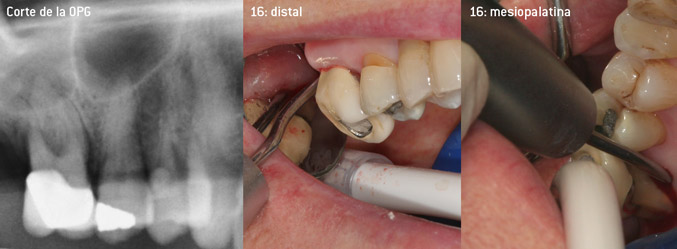

Como precursores del desarrollo de la nueva punta diamantada 3AP para eliminadores de sarro neumáticos, los dos odontólogos constataron que era necesario limitar el uso de las puntas diamantadas que se estaban comercializando hasta la fecha, sobre todo durante los tratamientos de furcaciones o en bolsas interradiculares estrechas. Además, esto debe llevarse a la práctica independientemente de si se trata de un procedimiento no quirúrgico (figura 2) o de un procedimiento quirúrgico (figura 3).

El objetivo principal consistía en desarrollar una punta de uso universal para no tener que perder tiempo al cambiar de punta de un tratamiento a otro. No obstante, también se pretendía que el uso de las nuevas puntas fuera más sencillo, tanto en bolsas periodontales estrechas desde el lado distal como en la entrada de furcaciones distales en los molares superiores, de manera que el tratamiento con instrumentos resultara más eficaz. Esto se consiguió aumentando el diámetro del arco del instrumento (figura 1), lo que representa una enorme ventaja durante el desbridamiento cerrado, sobre todo en el caso de piezas dentales con pérdida de adherencia avanzada y lesiones de furcación (figura 4).

Desbridamiento cerrado de la furcación de la pieza 16

Fig. 4: Desbridamiento cerrado de la furcación de la pieza 16 con pérdida de adherencia avanzada